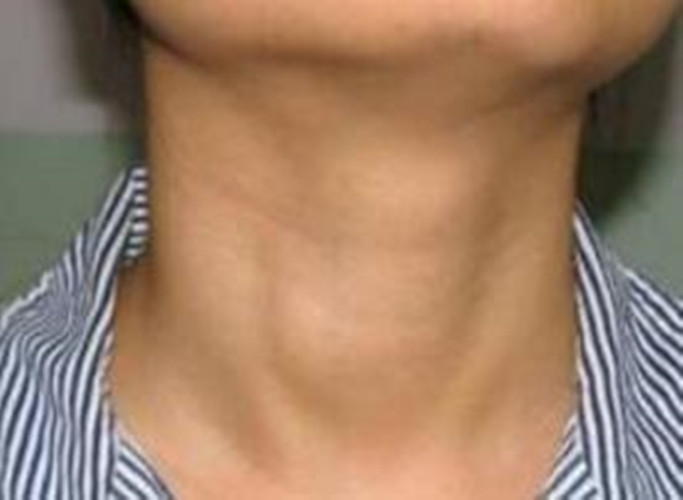

女人的喉腫瘤的表現

女人的喉腫瘤的症狀